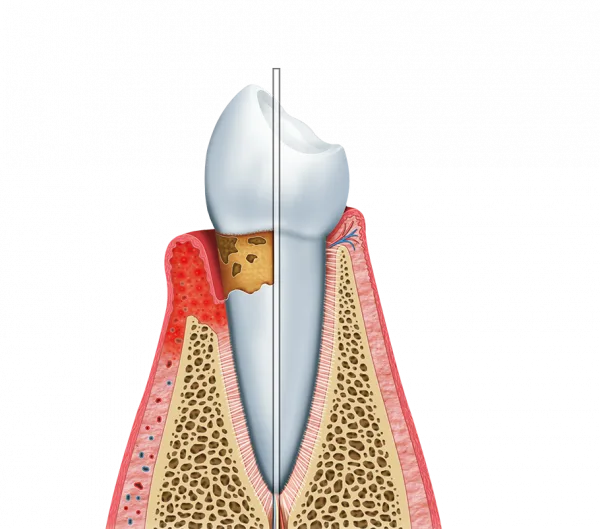

A prevenção de doenças periodontais é outro aspecto crucial do tratamento gengival.

Ao realizar o tratamento, o paciente evita problemas como gengivite e periodontite.

Essas condições podem levar à perda dentária se não forem tratadas adequadamente.